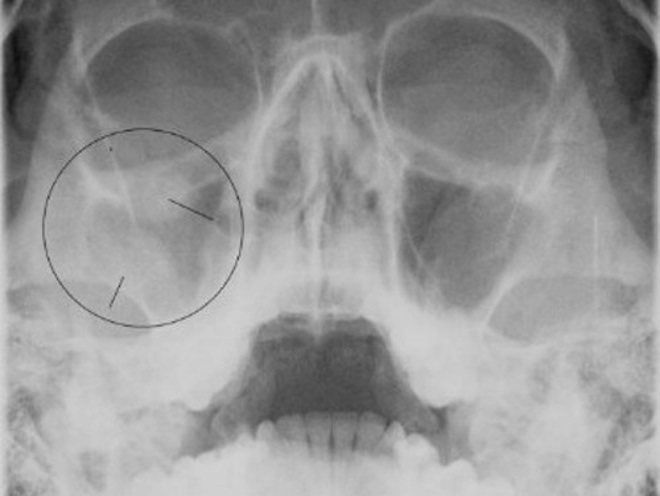

КТ-снимки хронического этмоидита: подробная визуализация